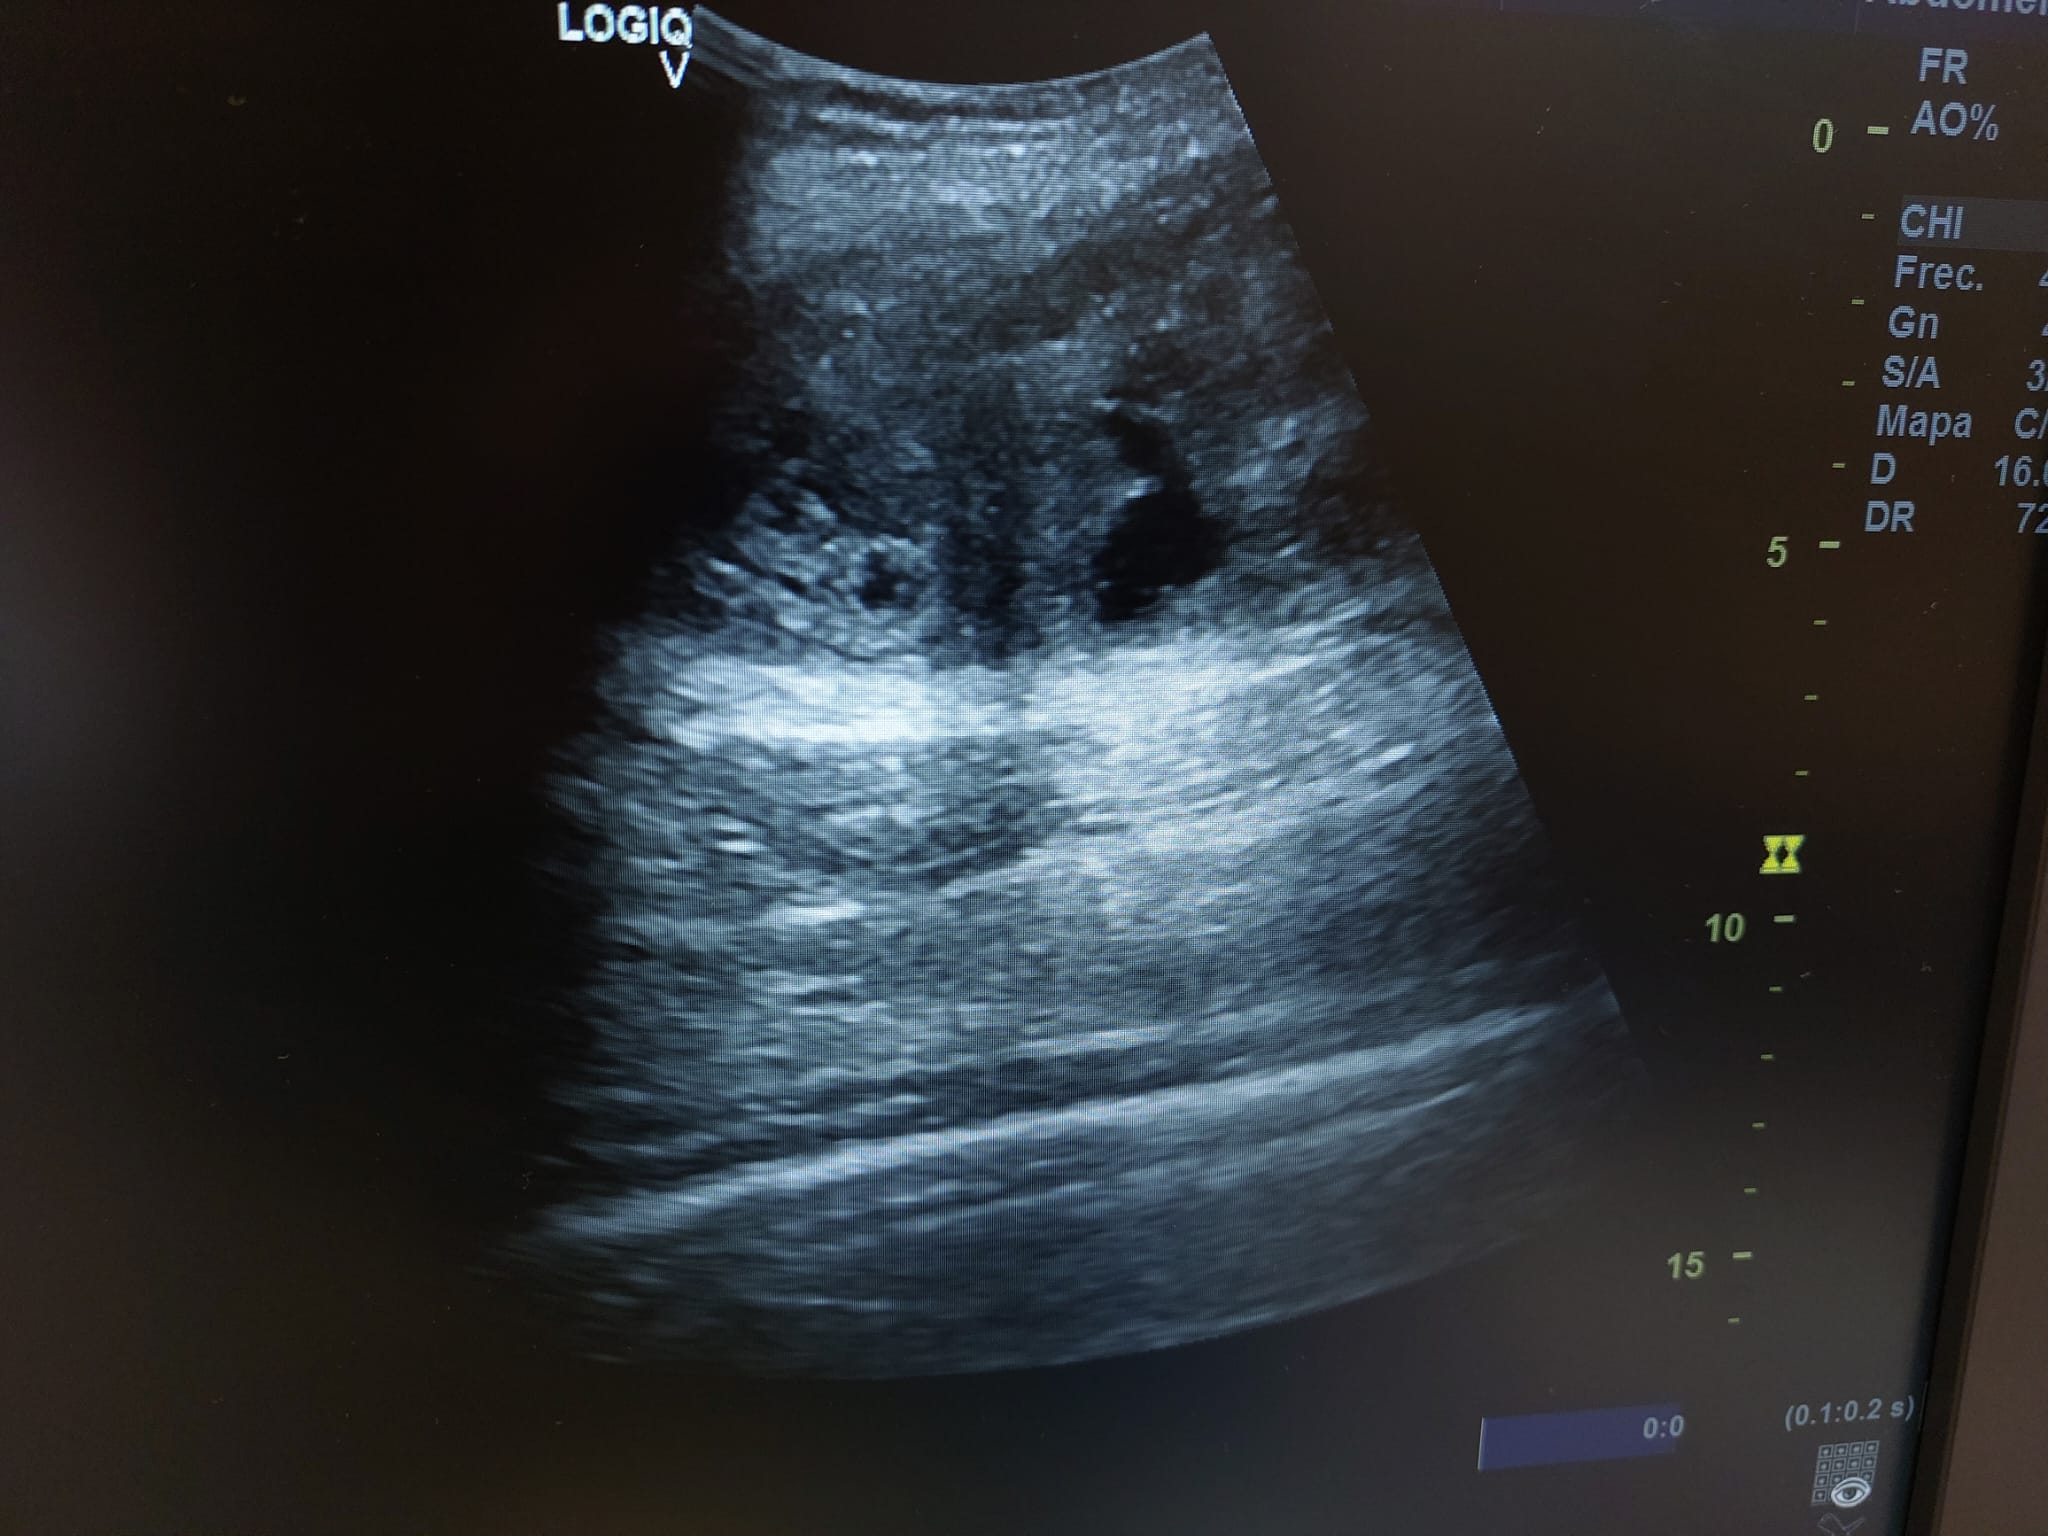

Se realiza ecografía observando colección anecoica a nivel muscular compatible con hematoma organizado, de aproximadamente 7 x 4 cm.

En el seguimiento se observa evolución tórpida sin mejoría clínica y en la ecografía de control se observa aumento notable de tamaño respecto al previo, estructura heterogénea de imagen anecoica con septos internos. Se aprecia edema intramuscular perilesional y captación al activar el Doppler. Se plantea la posibilidad de un hematoma sobreinfectado o, debido a su importante crecimiento, una probable etiología neoplásica. Tras hallazgos descritos en consulta, COT solicita de forma urgente la realización de RNM y biopsia de la lesión. Posteriormente, el resultado de las pruebas complementarias confirman diagnóstico de sarcoma histiocítico.